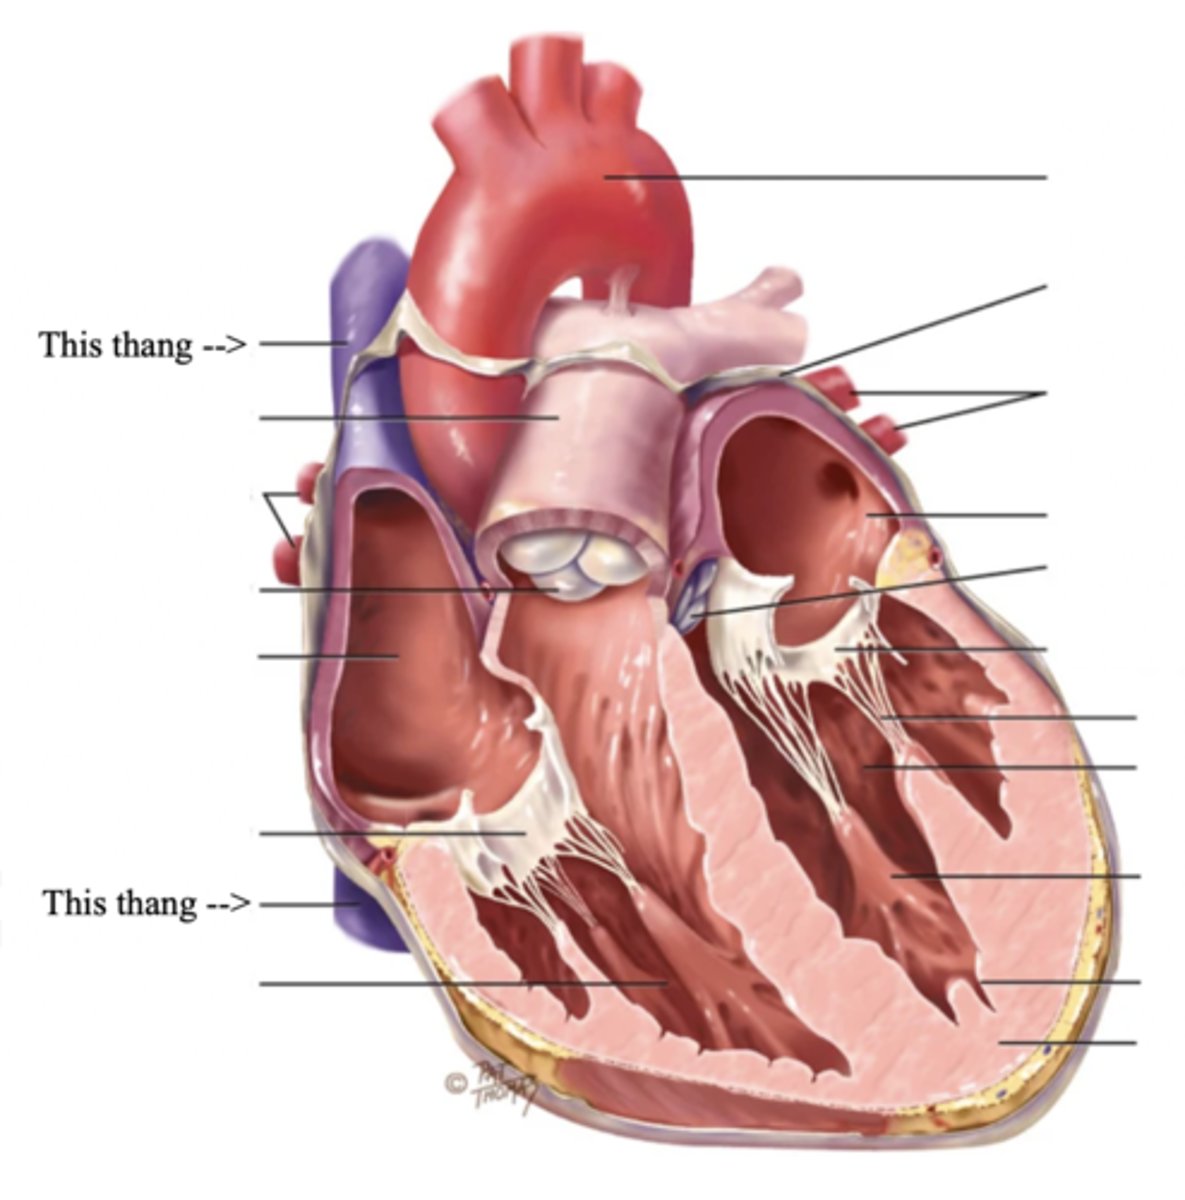

3 Layers of the Heart Wall

- Pericardium

- Myocardium

- Endocardium

Pericardium

Membrane surrounding the heart

Anatomy of the Heart

Myocardium

The muscular wall of the heart; does the pumping

Endocardium

The thin layer of endothelial tissue that lines the inner surface of the heart chambers and valves

The 4 Great Vessels of the Heart

- Superior/inferior venae cavae

- Pulmonary artery

- Pulmonary veins

- Aorta

Superior/Inferior Venae Cavae

The large veins that empty into the right atrium of the heart and return unoxygenated venous blood to the right side of the heart

Pulmonary Artery

Artery carrying oxygen-poor blood from the heart to the lungs

Pulmonary Veins

Veins carrying oxygenated blood from the lungs to the heart

Aorta

The largest artery in the body which carries oxygenated blood from the heart throughout the body